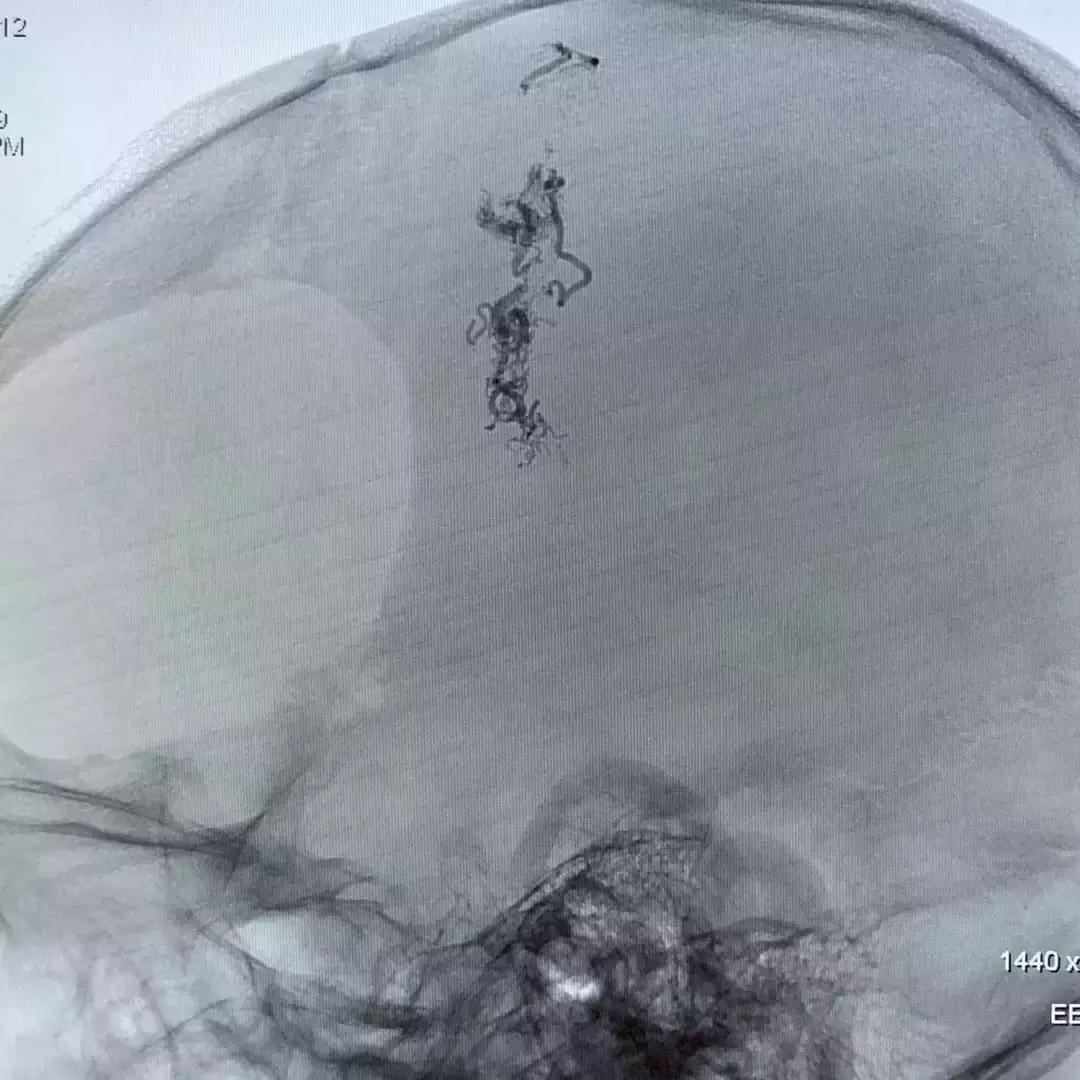

术中,刘加春教授通过这样的尝试锁定了两支动脉。如何注胶呢?由于血管结构原因,胶浓度不合适常常弥散不好,达不到畸形团“铸型”栓塞的效果。最后,刘加春教授决定采用稀释6倍的Glubran胶进行栓塞。

上图蓝色箭头为微导管的路径,可见多么曲折;红箭为胶在畸形团的铸型。

经过这样栓塞后,畸形得到绝大部分闭塞,结果很优美,但过程很惊心!

上图为栓塞后的造影